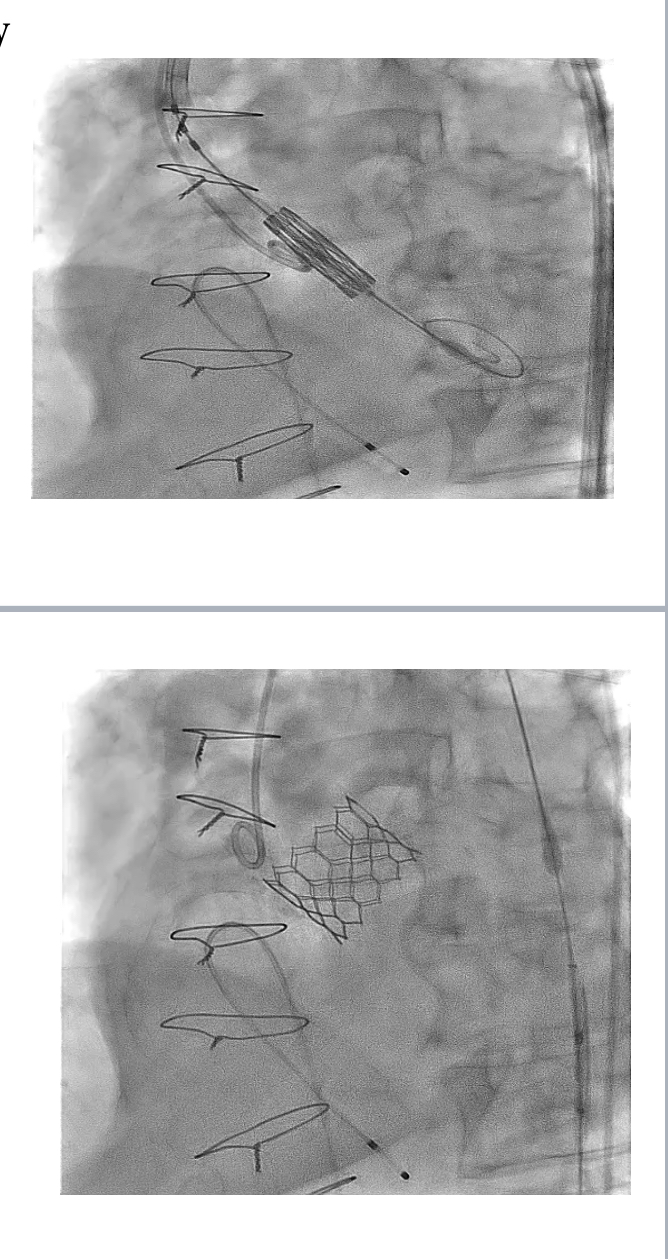

Pre-TAVI evaluation included a zero-contrast (dry) cardiac CT, TEE and femoral doppler ultrasound. Zero-contrast CT and TEE showed an AVA area of 617 mm2, perimeter of 89 mm, LM hight 17 mm, RCA hight 14 mm, mean sinus of valsalva and sino-tubular junction of 34 mm and 33 mm respectively. The femoral arteries were heavily calcified, with modertate torousisty and a minimal lumen diameter of 8.4 mm.After informed consent, the TAVI procedure was performed in the Hybrid Cathlab following the standard transfemoral approach. The femoral sheathes were inserted under flouroscopy and US guidance. The aortic valve was crossed and a Confida wire was palced in the left ventricle. The Pigtail was placed in the noncoronary cusp. A baseline aortogram was performed using Gadobutrol via automated injector. A 29 Sapien 3 ultra-valve (Edwards Lifesciences, Irvine, California) was deplyed after Gadobutrol aortogram to confirm the position.

Following informed consent, the TAVI procedure was performed in the hybrid catheterization lab via a standard transfemoral approach. Femoral sheaths were inserted under fluoroscopic and ultrasound guidance, and the aortic valve was crossed with a Confida wire placed in the left ventricle. A pigtail catheter was positioned in the non-coronary cusp, and a baseline aortogram was performed using Gadobutrol administered via an automated injector. A 29 mm Sapien 3 Ultra valve (Edwards Lifesciences, Irvine, California) was deployed after confirming its position with a Gadobutrol aortogram. The image quality was comparable to iodinated contrast media (ICM), and the procedure was successfully completed without any adverse reactions to Gadobutrol.

Following informed consent, the TAVI procedure was performed in the hybrid catheterization lab via a standard transfemoral approach. Femoral sheaths were inserted under fluoroscopic and ultrasound guidance, and the aortic valve was crossed with a Confida wire placed in the left ventricle. A pigtail catheter was positioned in the non-coronary cusp, and a baseline aortogram was performed using Gadobutrol administered via an automated injector. A 29 mm Sapien 3 Ultra valve (Edwards Lifesciences, Irvine, California) was deployed after confirming its position with a Gadobutrol aortogram. The image quality was comparable to iodinated contrast media (ICM), and the procedure was successfully completed without any adverse reactions to Gadobutrol.